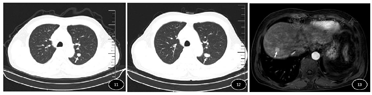

患者既往乙肝病史,乙肝表面抗原、乙肝表面e抗体、乙肝表面核心抗体阳性,病毒DNA定量为5.49×102 IU/ml,肝功能Child-Pugh A级,ECOG评分:0分。实验室检查:癌胚抗原及CA199在正常范围内,甲胎蛋白>1210.00 ng/ml;血常规示血小板65×109/L,余结果均在正常范围内。入院行腹部增强MRI提示:肝右叶占位(图3),大小约10.3 cm×10.7 cm×14.3 cm,动脉期不均匀强化,静脉期及延迟期强化减退,腔静脉、肝右静脉、肝门静脉右支及主干多发栓子形成(图1、图2);肝硬化、脾大,根据《原发性肝癌诊疗指南(2019年版)》,初步诊断为:1.原发性肝癌,CNLC分期:IIIa期;BCLC分期:C期;2.慢性乙型病毒性肝炎;3.肝硬化;4.脾大、脾功能亢进。

患者入院完善检查后,于2020年3月8日行肝穿刺活检,病理诊断回示:(肝穿刺)癌组织,倾向肝细胞癌。经多学科讨论,考虑患者无手术机会,建议行卡瑞利珠单抗免疫治疗联合阿帕替尼靶向治疗。经患者同意于2020年3月13日开始口服甲磺酸阿帕替尼(500 mg/d)靶向治疗联合静脉输注PD-1抗体卡瑞利珠单抗(200 mg/3周)免疫治疗及长期口服恩替卡韦片(0.5 mg/d)抗病毒治疗。患者用药后无明显原因出现发热,最高体温达38.0℃,行胸部CT及多次血培养检查未提示与感染相关,考虑与用药后肿瘤坏死引起无菌性炎症相关,给予对症治疗后较前好转。复查患者血常规及肝功能提示血小板、白细胞持续降低及转氨酶、总胆红素持续升高,血小板22×109/L,白细胞1.42×109/L,总胆红37.6 umol/L,谷草转氨酶341 U/L,给予对症治疗未见好转,根据NCI-CTCAE4.03标准,考虑出现应用靶向药物不良反应—严重骨髓抑制(3级)及肝功能损伤(3级),于2020年3月31日给予停用甲磺酸阿帕替尼,加用长期皮内注射胸腺肽(1.6 mg,2次/周)提高免疫力后上述症状较前好转。上述治疗方案治疗2个周期后复查腹部增强CT提示肝右叶占位及静脉癌栓较前缩小,甲胎蛋白降至788.0 ng/ml。患者头部皮肤出现少量皮疹,根据《CSCO免疫检查点抑制剂毒性管理指南》及NCI-CTCAE4.03标准,考虑患者出现与PD-1抗体治疗相关不良事件-反应性皮肤毛细血管增生症(1级),给予局部使用润肤剂后可耐受,未停药。治疗4周期后行腹部增强CT提示肝右叶占位较前范围缩小(图6),门脉主干癌栓及腔静脉癌栓消失(图4、图5),肝静脉右支及门静脉右支内癌栓较前缩小,甲胎蛋白降至117.5 ng/ml,影像学评价为部分缓解。再次行多学科讨论,考虑前期免疫联合靶向治疗有效,建议下一步行手术治疗,此外复查患者血常规示血小板49×109/L,考虑脾功能亢进未见好转,建议术中联合脾脏切除。排除相关手术禁忌后于2020年6月9日在全身麻醉下行"右半肝切除加脾脏切除加胆囊切除加肠粘连松解术"(图7、图8),术后恢复良好,无并发症,甲胎蛋白降至正常范围之内。术后病理(图9、图10)提示低-中分化肝细胞癌,侵及肝被膜,神经侵犯(-),脉管癌栓(+)。(脾脏)慢性瘀血性改变。(胆囊)黏膜慢性炎伴胆石症。(另送门静脉栓子)镜下炎症纤维背景中见大量凝固性坏死及组织细胞,未见癌累及。术后再次行上述方案治疗1周期后经多学科讨论,考虑患者具有高危复发因素:肿瘤直径大于5 cm,血管癌栓,中-低分化肝癌,建议继续行甲磺酸阿帕替尼(250 mg/d)靶向治疗联合PD-1抗体卡瑞利珠单抗(200 mg/3周)免疫治疗。上述方案再次治疗8周期后复查甲胎蛋白在正常范围值之内,复查胸部CT提示左肺小结节(图11),考虑患者术后出现肺转移,再次经多学科讨论,建议行肺转移灶局部治疗。于2020年12月14日在全身麻醉下行CT引导肺肿瘤碘125粒子植入术,术后恢复良好。继续治疗13周期后复查甲胎蛋白在正常范围值之内,复查胸部CT提示左肺下叶结节呈治疗后改变,较前增大(图12),考虑肺转移灶仍有活性,于2021年7年20日在全身麻醉下行肺部转移灶微波消融术,术后恢复良好。继续治疗1周期后复查甲胎蛋白仍在正常范围值之内,复查腹部增强MRI提示肝右叶异常信号(图13),考虑术后肝内复发,再次经多学科讨论,建议行肝内转移灶局部治疗。于2021年9月13日在局麻下行"B超引导下肝脏肿瘤射频消融术",术后恢复良好。目前患者定期复查规律应用上述方案,未见复发。